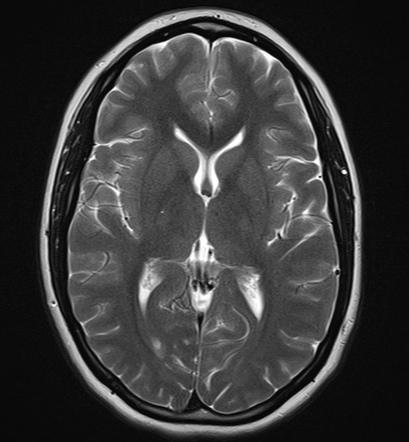

Obrázok vľavo ukazuje, ako asi vyzeral a vyzerá mozog priemerného zdravého človeka od dávnych čias až po súčasnosť, kedy sú obe hemisféry (racionálna aj intuitívna) v rovnováhe a symetrické. Druhý obrázok ukazuje, ako sa asi bude vyvíjať pod obrovským tlakom informácií a konzumácie všetkých tých videí a „zdieľaných“ článkov od množstva kamarátov zo sociálnych sietí. Intuitívna zložka bude výrazne potlačená a rácio v nás hypertrofuje rovnako ako tá jedna hemisféra. Kedysi ľudia aj pri výrazne obmedzených technických možnostiach vnímali prírodu a okolie oveľa intenzívnejšie a osobnejšie. Dnes mladého človeka ani nenapadne večer zdvihnúť hlavu a za jasnej oblohy sa pokochať pohľadom na hviezdy, ako sme to robili my a naši predkovia. Hviezdnu oblohu si dokáže „vygúgliť“ v oveľa väčšom rozlíšení, podobne ako rôzne animácie, prečo by mal byť taký retro… Ortodoxný „mobilmaniak“ už nedokáže ani vystrieť krk, ktorý mu stuhol v predklone, o čom hovorí tretí obrázok.